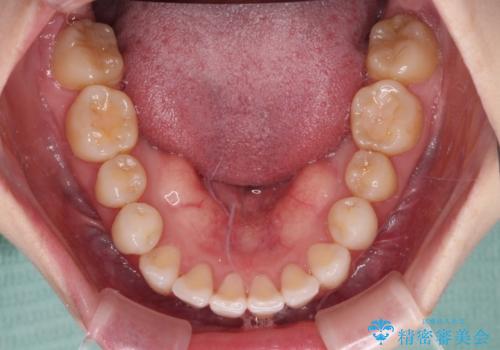

- 前歯のデコボコや八重歯の様になっていることを気にして来院された患者様です。

犬歯捻れて前方に飛び出しており、下顎前歯もそれに沿うようにデコボコとなっていました。

IPR(歯と歯の間を削る処置)によりスペースを獲得して上下顎前歯のデコボコを改善し、前歯が前方に突出しないように設定した上で、インビザラインにて矯正治療を行うこととしました。